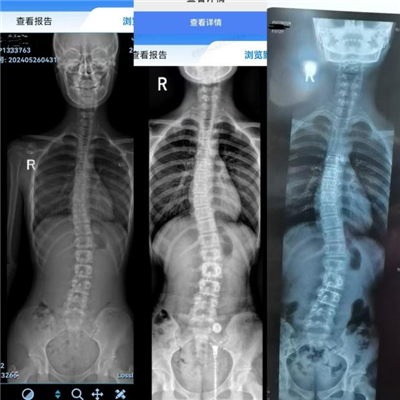

· 首次复查及调整治疗方案:时间来到 2024 年 2 月 16 日,小尹按要求到康复医学科门诊复查全脊柱 x 片。对比去年所拍摄的片子,发现脊柱侧弯改善情况不太理想。经过与小尹母亲深入的沟通交流,医师综合考虑后,建议在继续进行康复锻炼的基础上,引入浮针疗法进行介入治疗,期望以此来加速脊柱侧弯的恢复。为此,专门为小尹制定了浮针疗法 + 矫正锻炼 + 气血操的整体治疗方案。

· 辅助检查:2023 年 2 月 16 日全脊柱片显示,脊柱侧弯情况在胸腰段较为明显,cobb 角约为 15°。